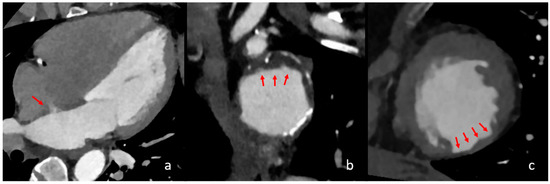

4.5. Previous Myocardial Infarction

- Blankstein, R.; Rogers, I.S.; Cury, R.C. Practical tips and tricks in cardiovascular computed tomography: Diagnosis of myocardial infarction. J. Cardiovasc. Comput. Tomogr. 2009, 3, 104–111. [Google Scholar] [CrossRef]

- Lardo, A.C.; Cordeiro, M.A.; Silva, C.; Amado, L.C.; George, R.T.; Saliaris, A.P.; Schuleri, K.H.; Fernandes, V.R.; Zviman, M.; Nazarian, S.; et al. Contrast-enhanced multidetector computed tomography viability imaging after myocardial infarction: Characterization of myocyte death, microvascular obstruction, and chronic scar. Circulation 2006, 113, 394–404. [Google Scholar] [CrossRef]

- Gosalia, A.; Haramati, L.B.; Sheth, M.P.; Spindola-Franco, H. CT detection of acute myocardial infarction. AJR. Am. J. Roentgenol. 2004, 182, 1563–1566. [Google Scholar] [CrossRef] [PubMed]